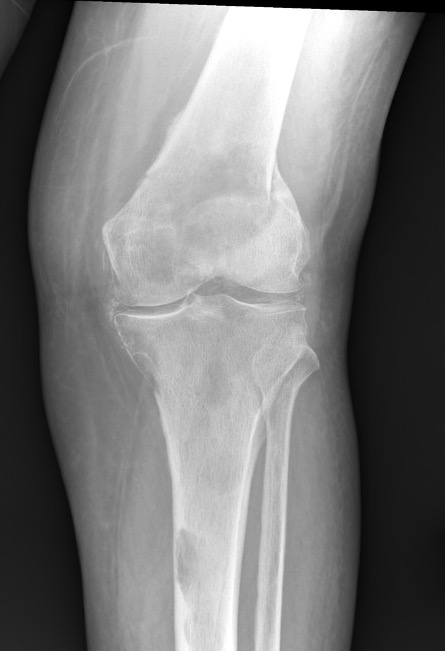

X-ray

1. Punched out lytic lesions

- axial and appendical skeleton

- widely disseminated

- soap bubble appearance

- no sclerotic reaction

2. Diffuse osteopenia

- in 15% to 25% of patients, no discrete lysis occurs

- diffuse osteopenia and osteoporosis are the only skeletal manifestations

3. Vertebrae Plana

4. Pathological Fracture

5. Pepper pot skull

Skeletal survey

Xray

- skull / spine / humerus / femurs / pelvis / chest & ribs

- low sensitivity

- only detect lesions with > 30% cortical destruction